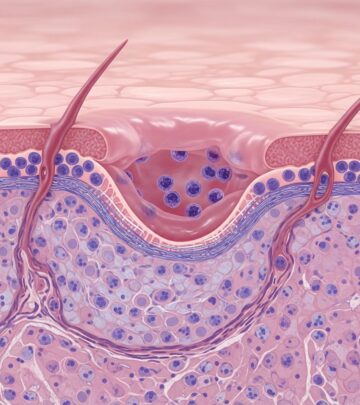

Acne: A Complete Guide To Causes, Symptoms, And Treatment